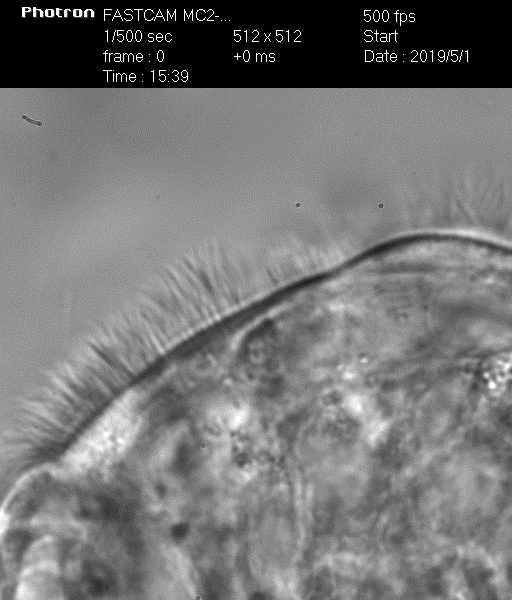

Биение ресничек у здорового – видео 1

Биение ресничек у больного ПЦД – видео 2